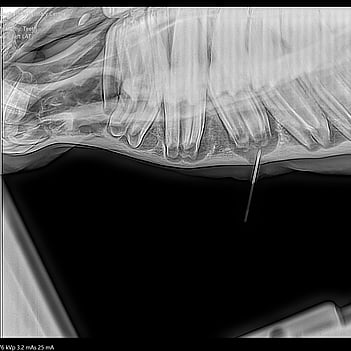

At VetSouth Equine, we use a full mouth oral speculum that allows the mouth to be safely opened. After the mouth has been thoroughly rinsed out with an antiseptic solution, the use of a light and mirrors enables full visualisation of the mouth.

The safe use of tranquilisers allows a thorough dental examination to be performed followed by effective treatment.The use of motorised power equipment ('Powerfloat') allows sharp enamel points, overgrowths and malocclusions of teeth to be quickly corrected. As a horse's teeth are continually growing or erupting, they will naturally develop sharp enamel points that can cut into the cheeks or tongue if left untreated. We recommend that your horse’s mouth and teeth are examined every 6 - 12 months depending on their age, dental history and oral conformation. This is often done at the same time as their annual vaccinations or at the horse’s annual health check.

Routine dental treatment and some minor surgical procedures (e.g. removal of wolf teeth) can be performed either at our client's premises or alternatively bought into the clinic. Horse's that require more advanced dental care (e.g. extraction of molar teeth or management of dental related paranasal sinus infections) are generally admitted to the clinic.